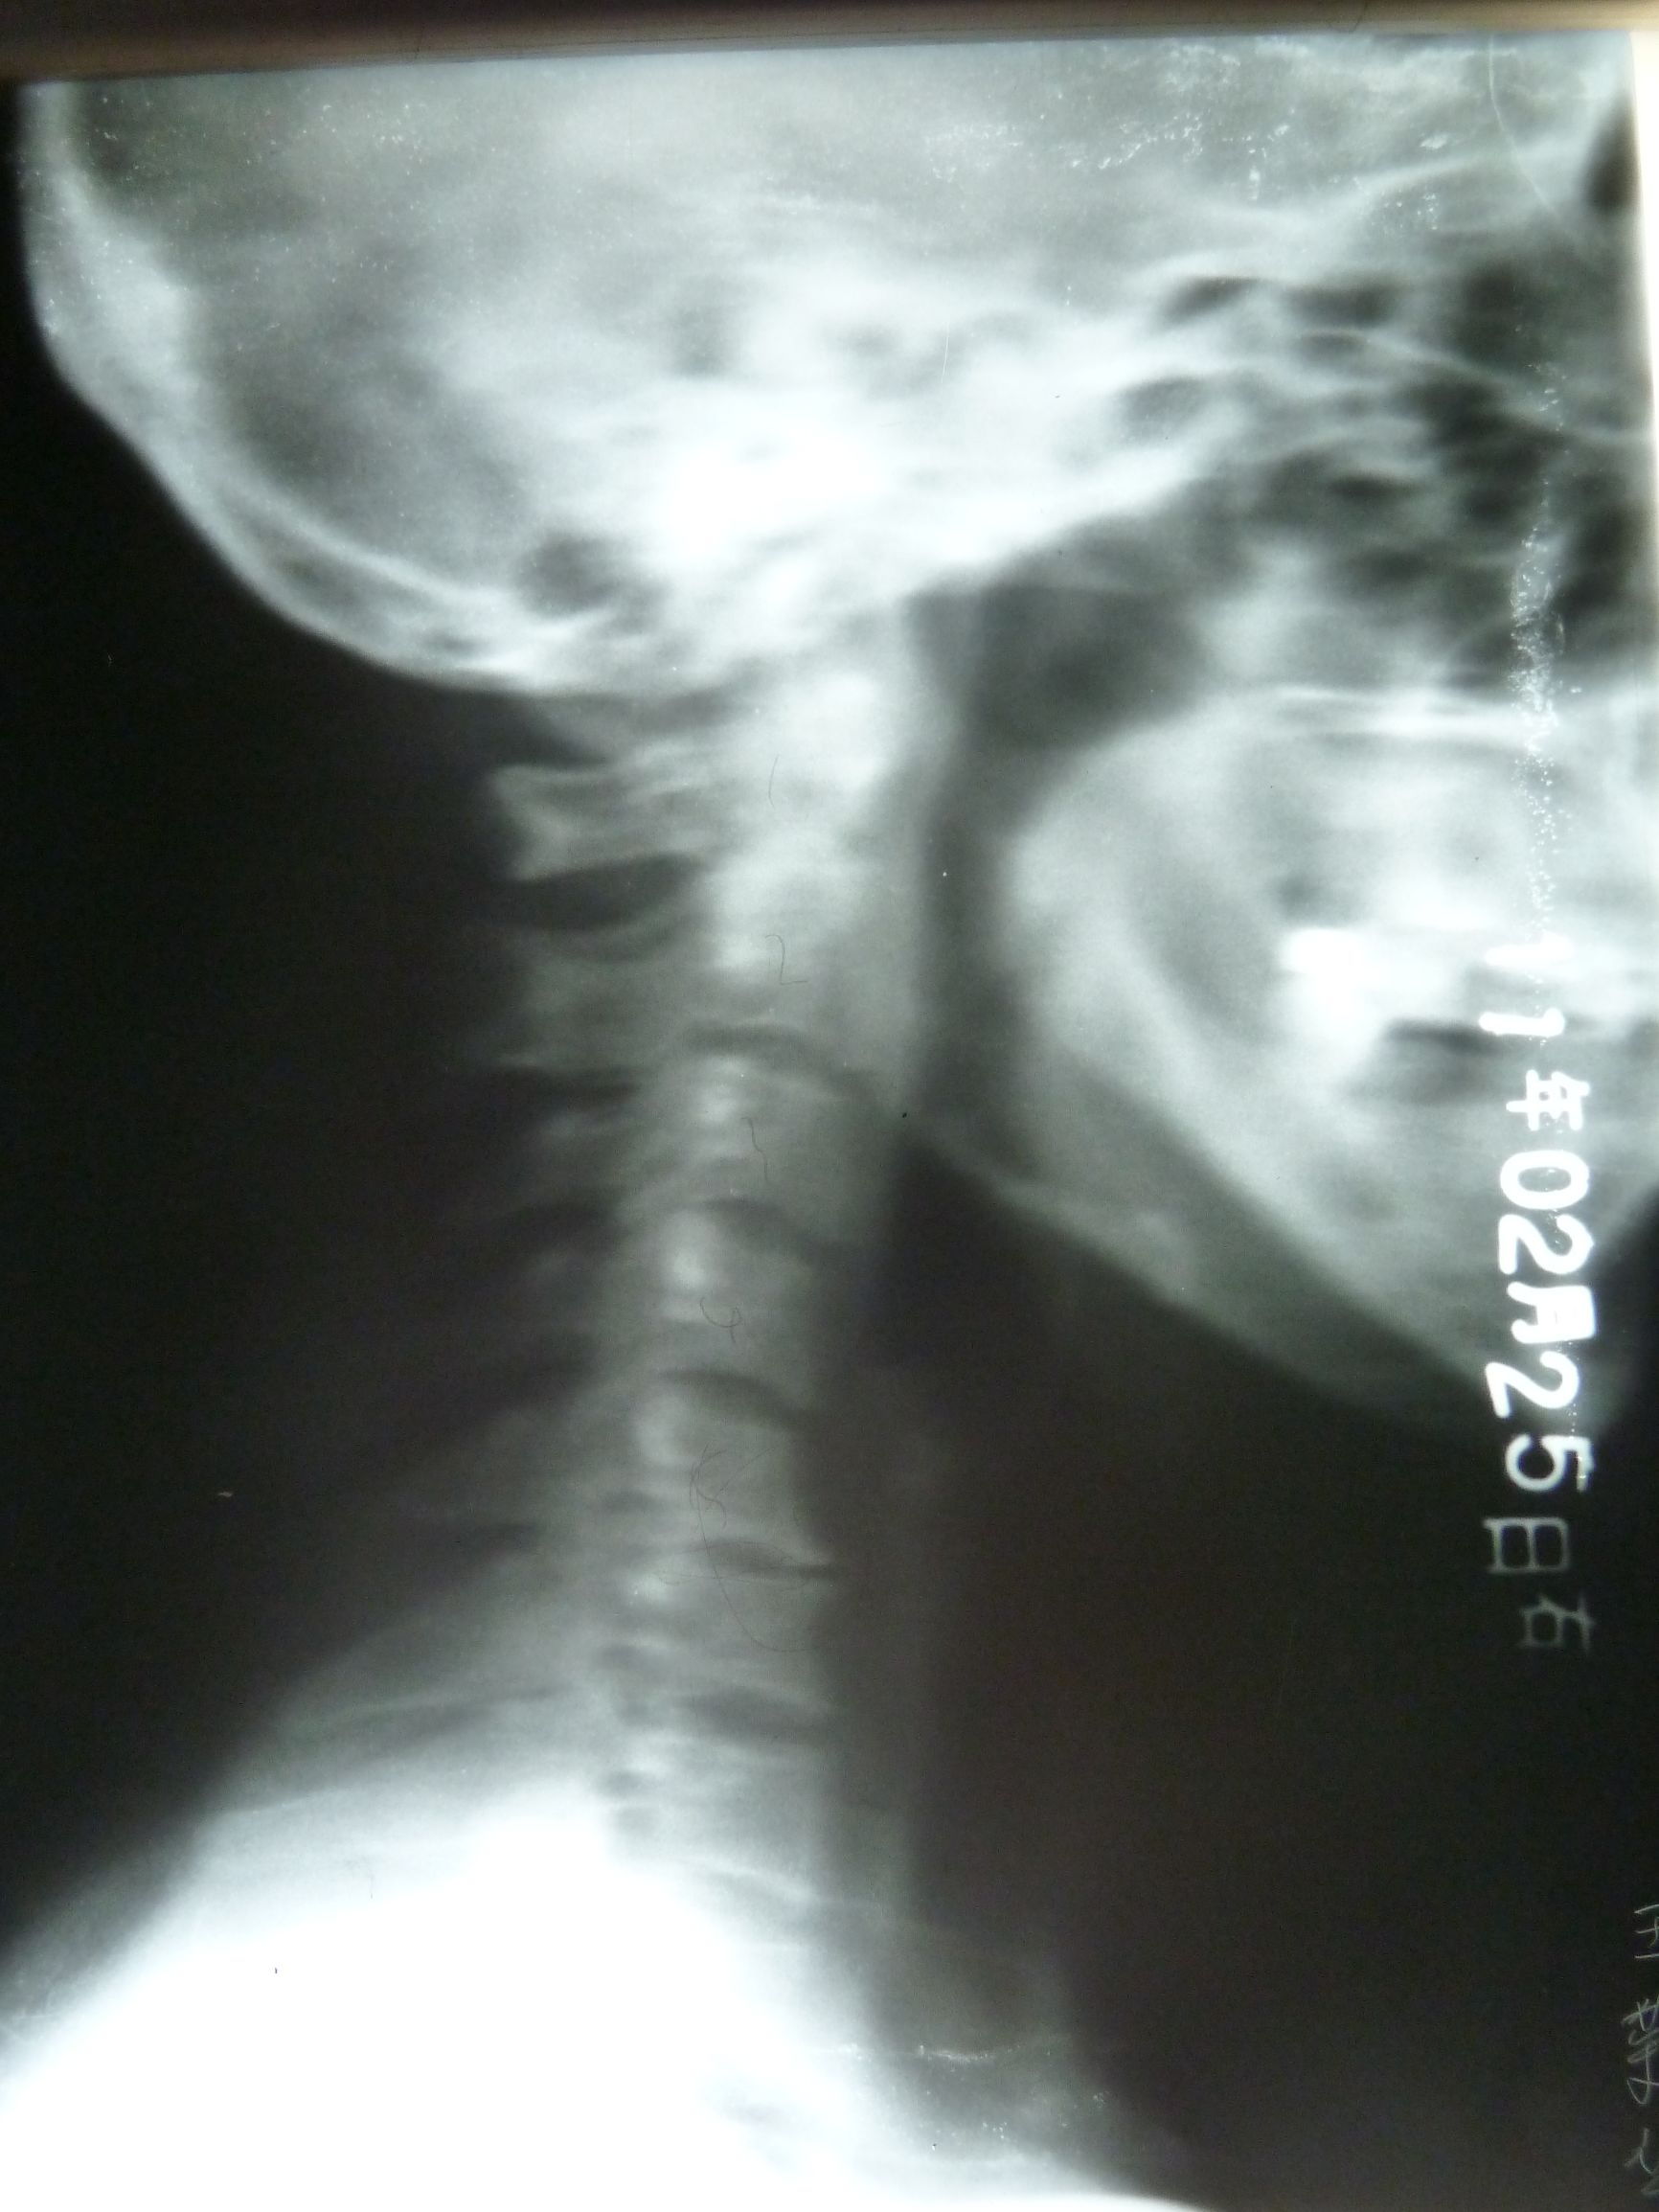

颈椎生理曲度变直:整个颈椎呈一条直线,脖子会很容易感到累,甚至会有疼痛,而生活中几乎80%的人都是直的。颈椎变直后,椎间盘和椎体前缘受力就会增大,久而久之椎间隙变窄,开始出现轻微骨质增生,如果不加以矫正,椎间盘就会突出、骨质增生会进一步加重。